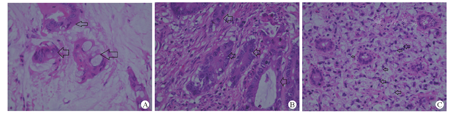

本组病例病理特征见表1。①肿瘤部位:结肠5例,以横结肠多见,直肠1例。②病理诊断:黏液腺癌2例,印戒细胞癌3例,管状腺癌1例,均有区域性淋巴结转移(图1A, 图1B, 图1C)。20 ~ 30岁组以管状腺癌及低分化型为主,而50 ~ 60岁年龄组则以管状腺癌为主(表2)。③病理中还发现1例横结肠肿瘤同时存在有肠壁肠神经元发育异常,例6自2岁起有典型便秘史。④例2十年前曾在外院做肝母细胞瘤切除术,术后常规辅以化疗,此次为二次肿瘤。